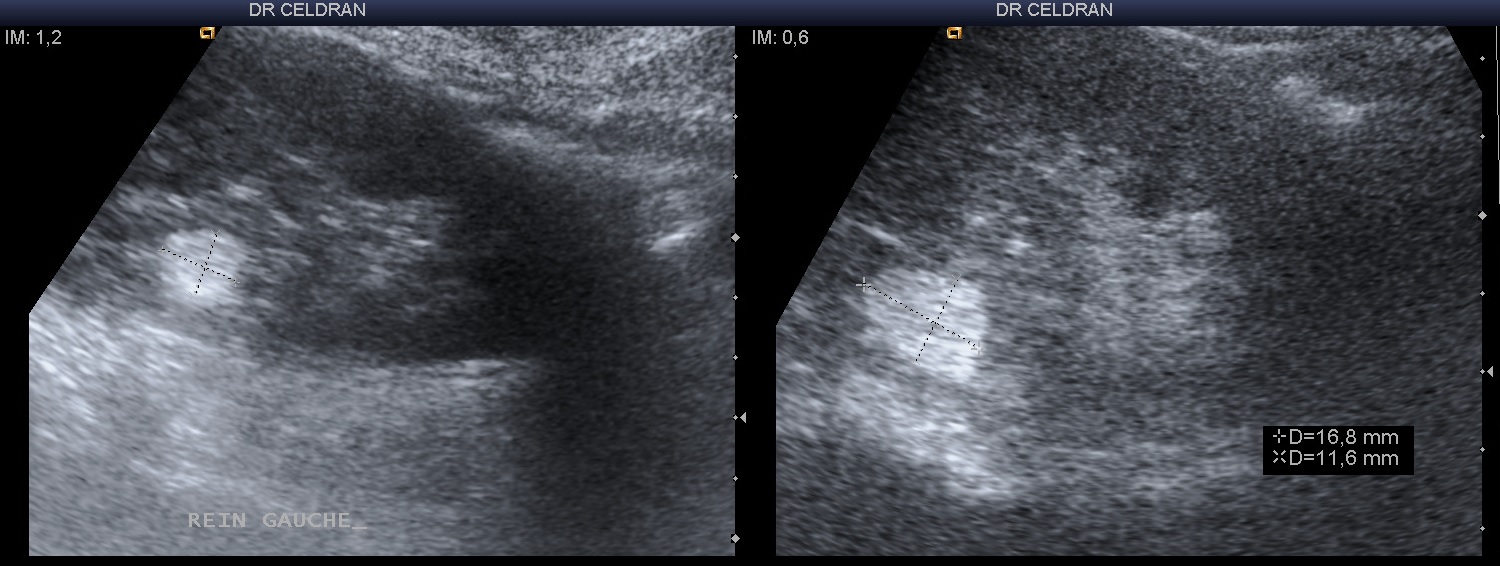

Reins Angiomyolipome du rein: les causes, le diagnostic et le traitement .Angiomyolipome du rein droit ou gauche, également accessible pour l'examen par ultrasons et même sa biopsie à l'aiguille fine L'échographie faite chez tous nos patients a retrouvé un aspect hyperéchogène hétérogène dans tous les cas.

Patiente de 58 ans Douleurs abdominales brutales sans notion de traumatisme Déglobulisation. L'angiomyolipome rénal est une tumeur bénigne solide du rein L'angiomyolipome est la tumeur bénigne la plus fréquente des masses dolides du rein, elle représente un cadre de fréquence de 1 à 3% des tumeurs du rein, sa composition histologique est faite de trois contingents: graisseux, fibres musculaires lisses et vasculaires a des proportions variables, elle sévit sur un cadre sporadique et peut s'exprimer dans un cadre congénitale.

Patiente de 58 ans Douleurs abdominales brutales sans notion de traumatisme Déglobulisation. L'échographie faite chez tous nos patients a retrouvé un aspect hyperéchogène hétérogène dans tous les cas. Il apparaît souvent chez des personnes atteintes de sclérose tubéreuse, un trouble génétique qui engendre la formation de tumeurs non cancéreuses dans de nombreux organes, dont les yeux, la peau, le cerveau, les poumons, le cœur et les reins.